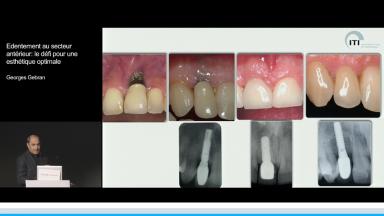

Edentement au secteur anterieur: le défi pour une esthetique optimale

Georges Wadih Gebran

A partir de la description des facteurs de risque esthétique du bloc incisivo-canin maxillaire, de la présence d’os et de gencive autour des implants, le conférencier présente une succession de cas cliniques décrivant ses procédures chirurgicales et prothétiques.

• de déterminer le bon timing de chirurgie implantaire post extractionnelle

• de réfléchir sur la préservation à moyen-long terme de l’os autour des implants